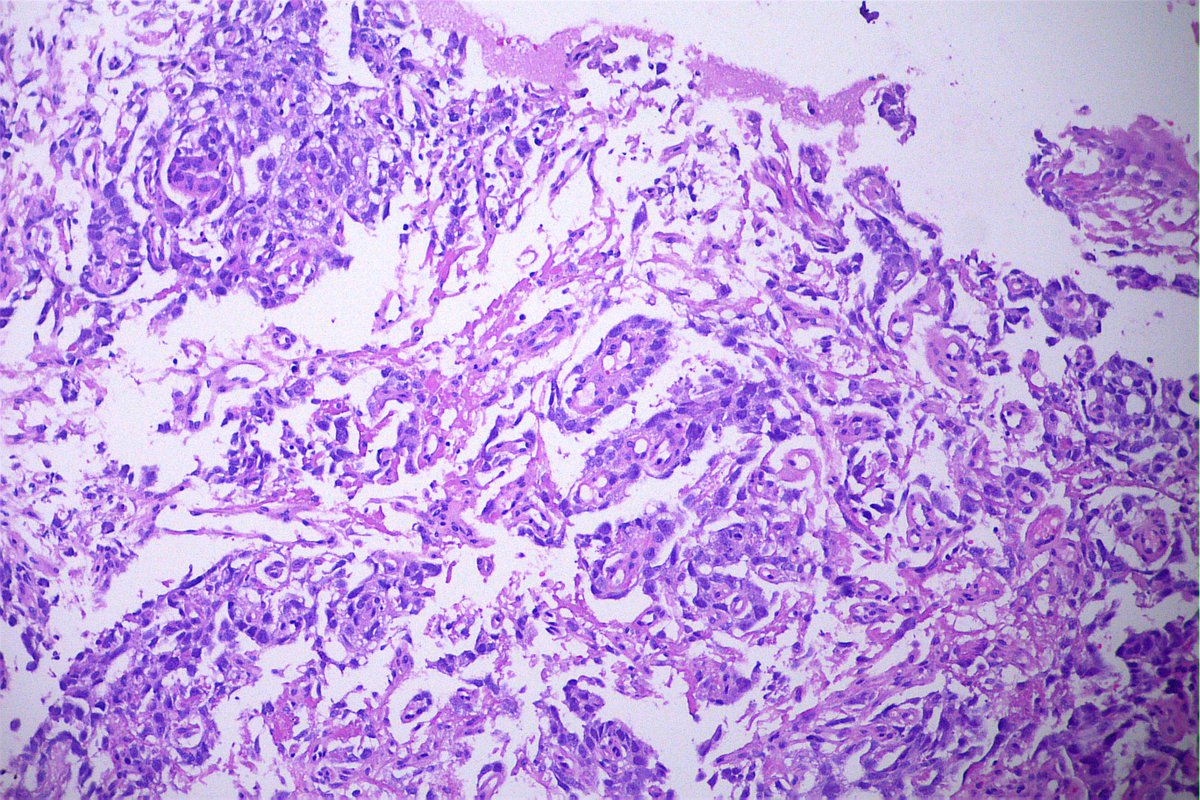

Case of the day. M, 30 years old, with weight loss, pulmonary consolidation area, mediastinal lymph node enlargement, and endobronchial polypoid lesions. Bronchial biopsy performed. #pulmpath #pathology